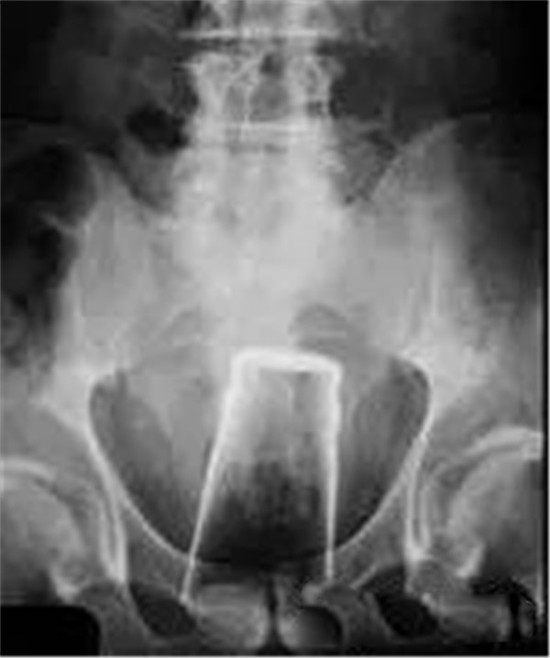

大肠里的擀面杖。男性

这是做饺子皮用的擀面杖。对,全部塞进去了。你知道怎么看男女吗?看骨盆的角度。

取出的方法如同上面。